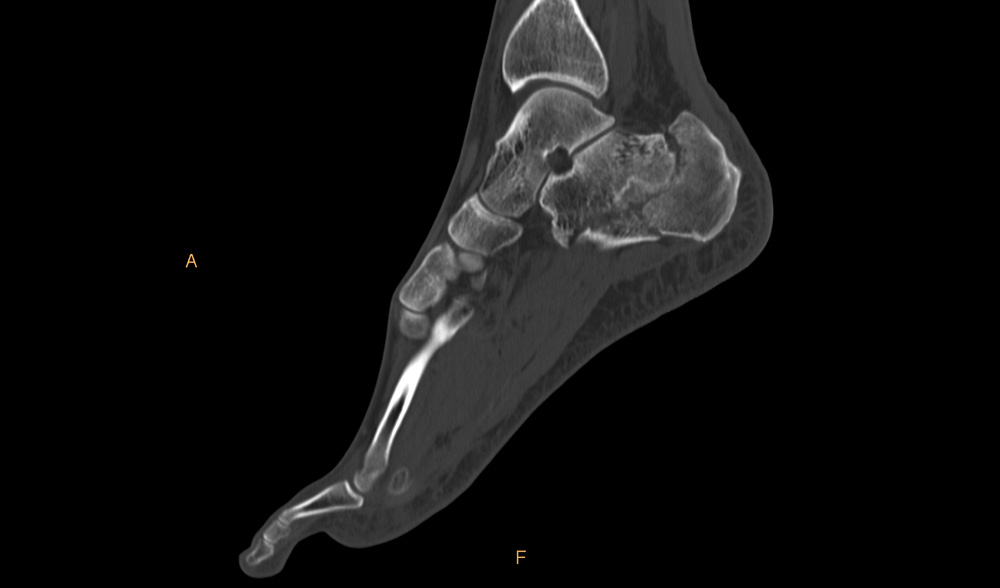

W celu potwierdzenia złamania kości piętowej wykonywane jest badanie RTG. Obecnie obowiązującym badaniem w złamaniach kości piętowej jest tomografia komputerowa. Dopiero w tym badaniu można dokładnie określić charakter złamania – ilość odłamów, przebieg szczelin złamania, a także stopień przemieszczenia odłamów.